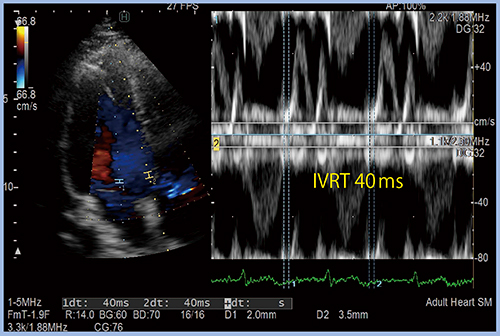

実臨床においては,上記の診断アルゴリズムで拡張機能障害を分類できないことがある。その代表例が心房細動や僧帽弁逆流であり,左房圧評価に特別な判断を要する。エコー指標としては,心房細動では心室中隔のE/e’や等容弛緩時間(IVRT)など5項目,僧帽弁逆流ではIVRTやIVRT/Time to E to e’(IVRT/TE-e’)など4項目がガイドライン3)に示されている。IVRTは非常に重要な項目であるが,計測には特別なソフトウエアが必要である。また,TE-e’は,ドプラの時相を細かく分析することで,隠れた拡張機能障害を見つけ出すための指標である。

日立製の超音波診断装置に搭載された“Dual Gate Doppler”は,左室の流出路と流入路のドプラ波形を同時に計測できるため,IVRTを正確に計測でき有用である(図1)。

図1 Dual Gate DopplerによるIVRTの計測